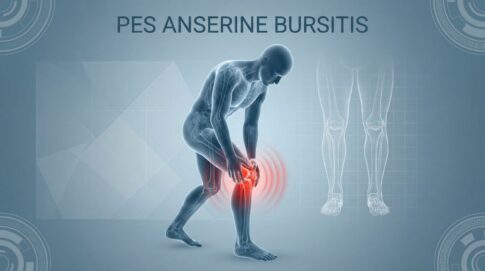

スポーツ障害なぜ鵞足炎にオステオパシーが選ばれるのか 大阪市で鵞足炎(がそくえん)にお悩みの方へ。 膝の内側の痛みが階段の上り下りや立ち上がりの際に強くなる、その症状は鵞足炎の可能性があります。 オステオパシー整体院トラストでは、鵞...